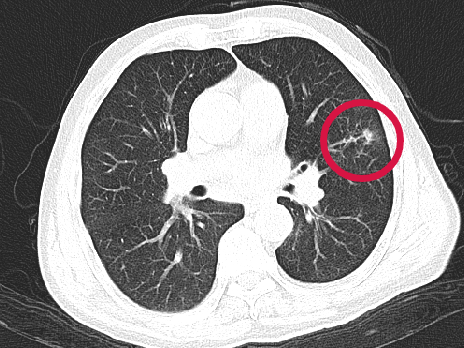

術(shù)前圖像

▲患者因體檢發(fā)現(xiàn)左肺上葉舌段結(jié)節(jié),考慮周圍型肺癌可能。因高齡、肺氣腫無法手術(shù),遂來院接受肺結(jié)節(jié)冷凍消融治療,術(shù)后病理為肺癌,定期隨訪提示腫瘤逐漸縮小。